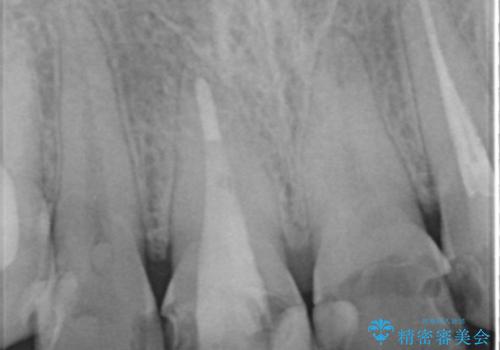

精査したところ、ほとんどの歯が保険内のレジンで充填されており、咬み合わせも悪く咬合していない歯もありました。

虫歯をしっかりと治療したのち、オールセラミッククラウンによる補綴治療を行いました。